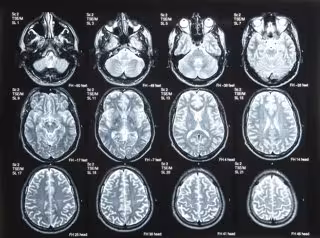

Cerebro

GETTY